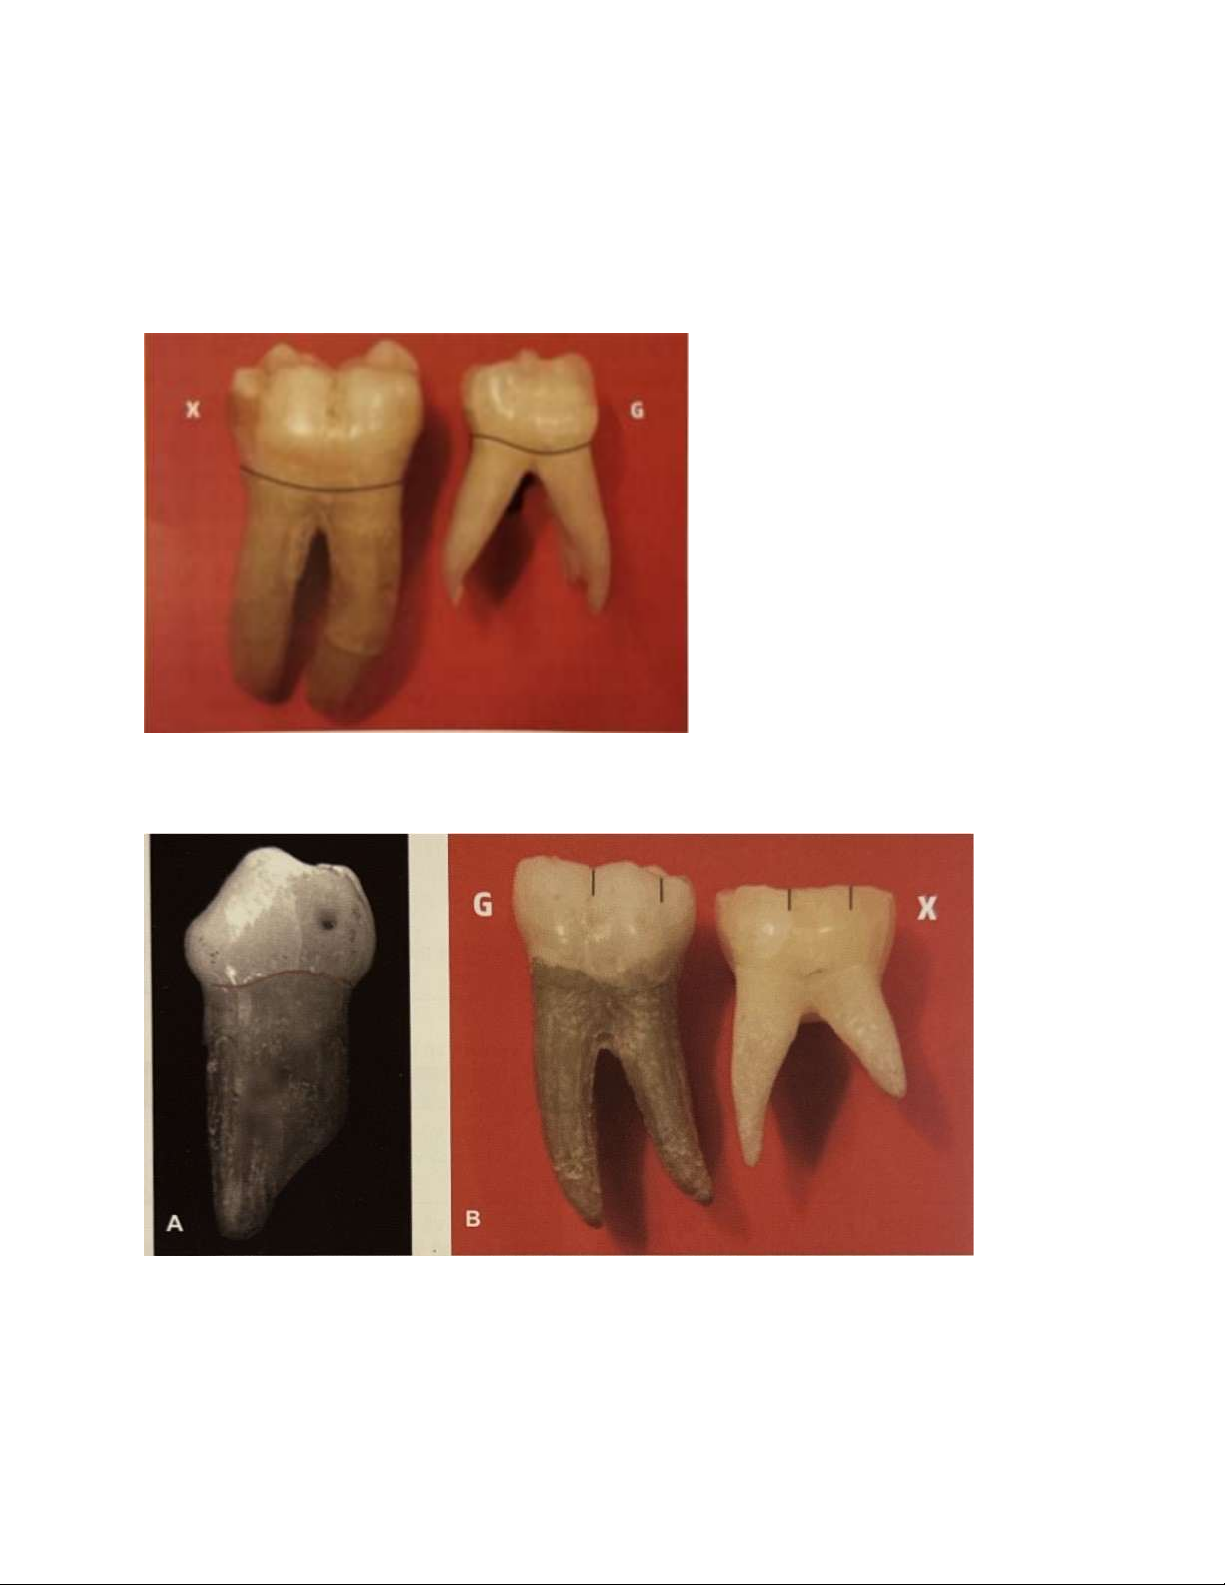

Hình 10. So sánh răng cối sữa thứ hai và răng cối lớn vĩnh viễn thứ nhất, lưu ý các

đặc điểm răng cối sữa: cổ eo thắt, chân xoè rộng, thân chung rất ngắn.

Hình 11. A, Răng cối sữa thứ nhất hàm dưới nhìn từ phía gần với mặt ngoài và mặt

trong hội tụ về phía nhai dẫn đến thu hẹp mặt nhai rất nhiều. B, Hình ảnh so sánh

răng cối sữa và răng cối lớn nhìn từ mặt ngoài. Cả hai răng đều có 3 múi ngoài lOMoAR cPSD| 59561451

nhưng tương quan kích thước khác nhau. Răng cối sữa có ba múi gần bằng nhau,

khác với răng cối lớn thứ nhất vĩnh viễn có múi xa nhỏ nhất.